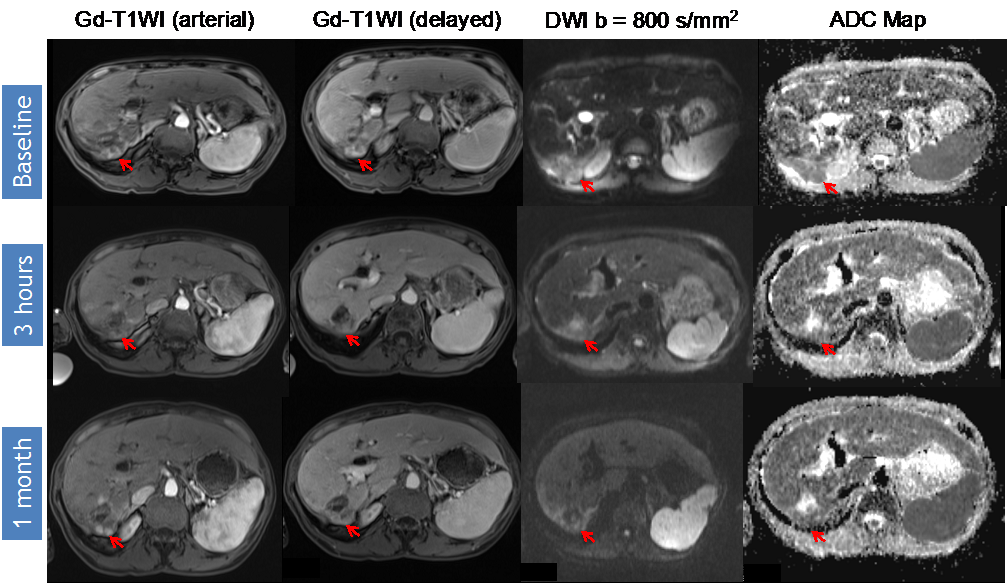

DWI (diffusion-weighted imaging) Response Assessment after DEB-TACE (drug-eluting bead transarterial chemoembolization). 65-year-old man presented with a segment VIII HCC (hepatocellular carcinoma) (arrow) without macrovascular invasion or extrahepatic disease. Note that there is no significant change in the post-treatment arterial Gadolinium (Gd)-enhancement pattern; although there is mild increase in the delayed Gd-enhancement over time. However, when analyzing DWI images, ADC (apparent diffusion coefficient) values increased progressively for ≥20% (baseline ADC 0.808 × 10−3 mm2/s, post-3 h ADC 1.60 × 10−3 mm2/s, post-one month ADC 2.30 × 10−3 mm2/s and post-three month ADC 2.80 × 10−3 mm2/s), and visually, the central area of restriction is no longer noted. The findings represent a subjective and objective measurement of response, in this case representing complete response (CR) to therapy.

Identifying early disease progression or absence of response to locoregional therapies is imperative and allows for individualized therapeutic strategies and potentially improved overall prognosis in patients. Volumetric ADC changes after conventional TACE (cTACE) have been investigated at one month after therapy and correlated with six-month RECIST and mRECIST objective responses [27]. Increases in volumetric ADC values to 1.6 × 10−3 mm2/s in at least >39.8% of the tumor volume correlates with objective response by mRECIST at six months with a sensitivity of 88.4% and specificity of 78.6% (p = 0.001). Similar results were obtained by using RECIST response criteria, albeit with lower sensitivity and specificity [27]. An absolute increase in ADC values has also been observed in responding lesions compared to non-responders by mRECIST criteria for cTACE [28]. Kokabi et al. [29] demonstrated a % ADC increase for responders vs. non-responders (36.4% vs. 7.4%; p < 0.001) 3 h after DEB-TACE intervention, which further increased after one and three months (98.1% and 115.2%) for responders, whereas no relevant increase for non-responders (−0.1% and 2.1%, p > 0.05) was evident. Exemplary diffusion-weighted imaging cases from this study with complete response (Figure 1), partial response (Figure 2), and progressive disease (Figure 3) are illustrated below. A significant percent increase in ADC values has also been reported by another study in responding lesions one and three months post-DEB-TACE compared to non-responders by mRECIST and EASL criteria [30].

Variable timelines in terms of changes in DWI were reported with some studies demonstrating significant changes in treated lesions within 24 h [29,43,46], 2–3 days [10] or 5–7 days [45] after therapy, all of which could predict the outcome. However, another study only detected a significant ADC change following 1–2 weeks after treatment but not before or after that time period [47]. Kokabi et al. [29] demonstrated a continuous increase of obtained ADC values during the course of three months for objective treatment responders but not for non-responders after DEB-TACE (Figure 1, Figure 2 and Figure 3). Chung et al. [46] investigated intraprocedural DWI changes following cTACE and did not detect a significant % ADC change (3%; SD: ±16.4%) in treated lesions. However, an intraprocedural relative ADC value increase or decrease of ≥15% of individual lesions was associated with a 100% positive predictive value, a specificity of 100%, and a sensitivity of 46% for tumor response after 1 month (EASL) following cTACE.